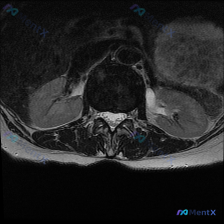

刚整理了一份很有警示意义的读片病例,分享给大家,这个坑平时读片真的很容易踩。 病例基本信息 临床诉求:患者因腰痛就诊,临床怀疑椎间盘病变,提供一张腰椎MRI T2加权轴位影像请读片。 影像基础评估 这是一张腰椎横断面(轴位)T2加权影像,清晰度和信噪比都不错,没有明显运动伪影,可以清楚辨认椎体、椎弓...

刚整理了一份腰椎MRI读片病例,只有单张轴位T2加权图像,把完整的分析思路整理出来和大家分享。 一、影像基本信息 这是一张腰椎MRI轴位T2加权图像,清晰度良好,解剖结构辨识度高: - 扫描水平为腰椎单个节段(大概率L4/5或L5/S1,具体需结合矢状位确认) - T2序列特征符合典型表现:脑脊液高...

整理了一份腰椎MRI读片讨论,给大家分享一下思路。 病例影像基础信息 本次仅提供放射影像-腰椎MRI-T2序列-轴位单张图像,扫描层面为腰椎某一节段,视觉判断符合腰4/5或腰5/骶1椎间盘水平,无临床病史、体征及其他检查资料,核心问题是明确该层面是否存在椎间盘病变相关影像学表现。 影像具体读片结果...